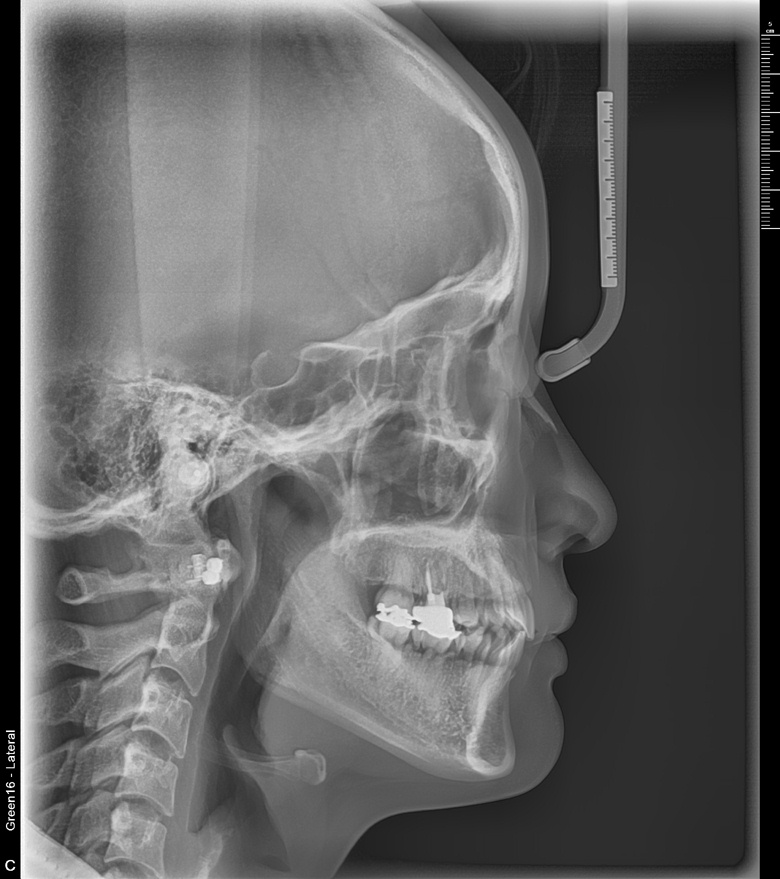

치료 후 사진입니다.